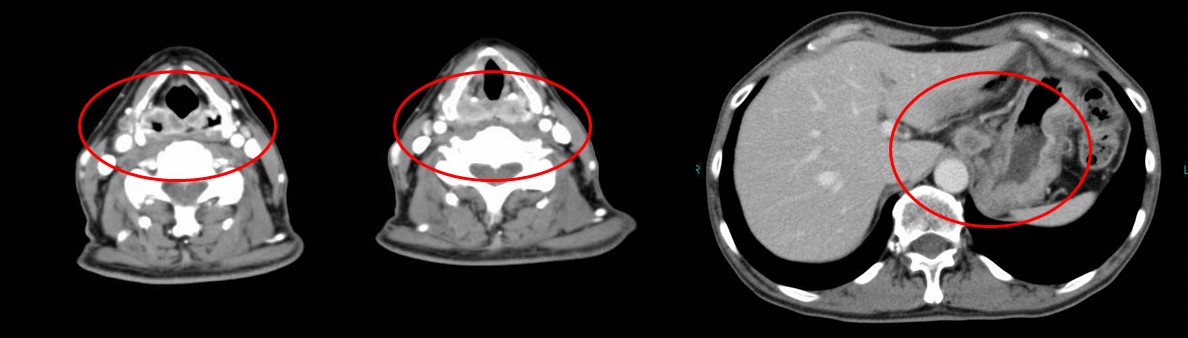

父の癌細胞が消滅したct Mri画像 難病 末期癌からの生還